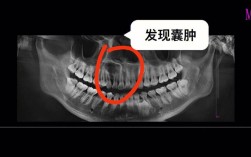

- 牙髓坏死导致牙齿失去支撑: 蛀洞深及牙髓(牙神经),导致牙髓感染坏死,感染会扩散到牙根尖周围,破坏牙槽骨,最终导致牙齿松动,如果松动非常严重,可能在咀嚼或轻微外力下脱落,这也不是“自己掉”,而是因感染破坏了支撑结构。